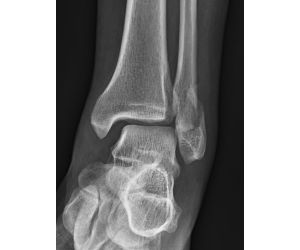

Ankle Fracture with Intercalary Fragments - Update

Maximilian Heitmann

Following up on my previous post that showed the preoperative CT slices. https://lnkd.in/e74BVTPn See also this previous case discussion...